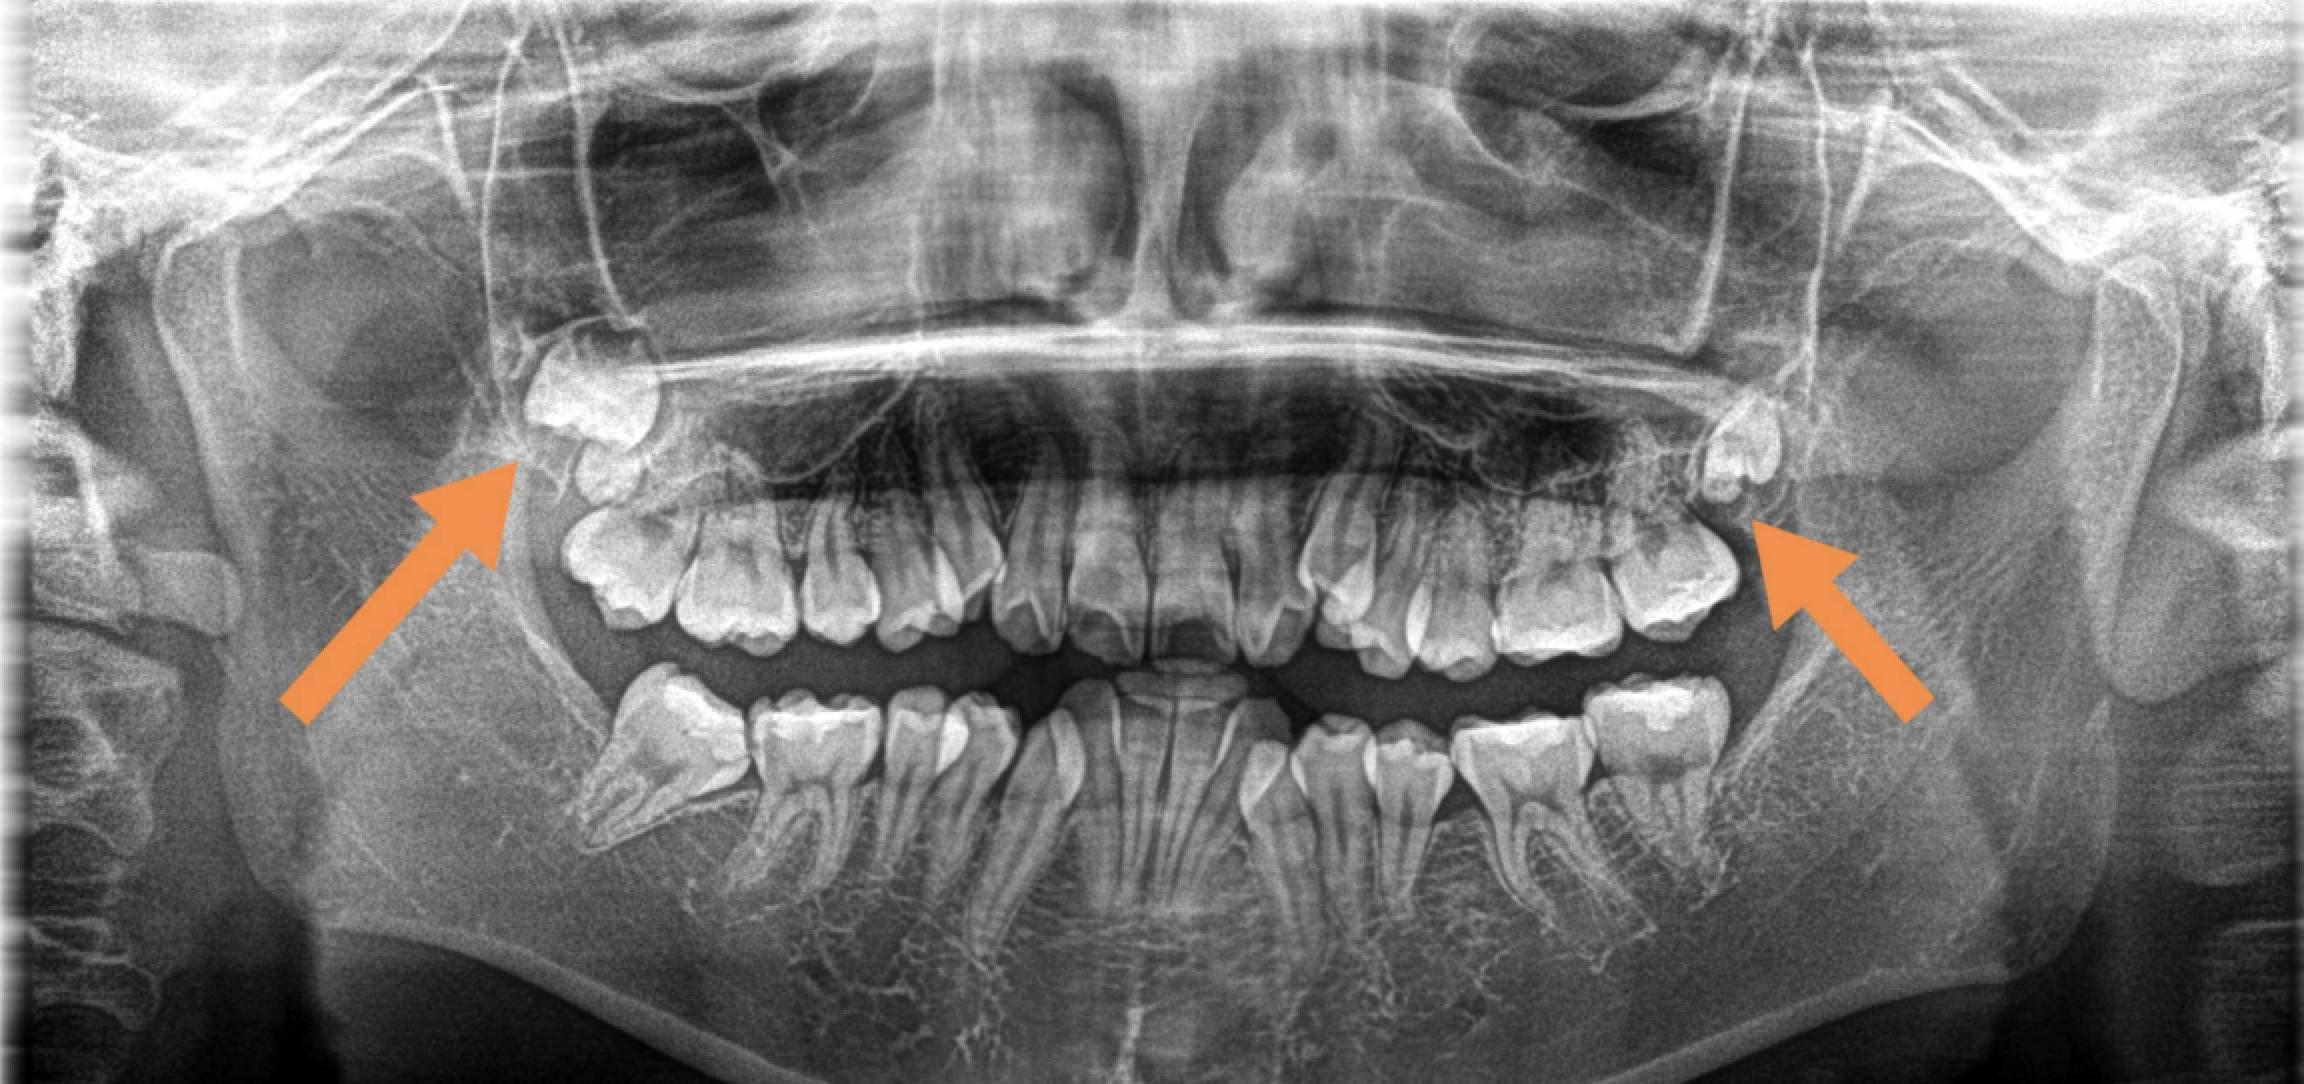

其實(shí),這些就是我們俗稱的阻生牙。

這一類智齒比較難拔,基本上都是微創(chuàng)手術(shù)了,但也需要切開牙齦操作,手術(shù)難度還是不低的。因此價(jià)格相比前兩種手術(shù)會(huì)高一些。

下頜智齒水平生長(zhǎng)

當(dāng)然,還有其他更加奇奇怪怪的pose……

各類“不聽話的”下頜智齒